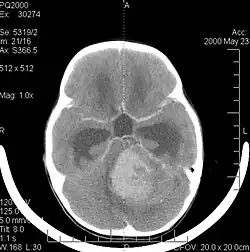

Medulloblastom im Schädel-CT nach Kontrastmittelgabe bei einem sechsjährigen Mädchen.

In der Computertomographie (CT) und Magnetresonanztomographie (MRT) stellen sich Medulloblastome als solide Raumforderungen mit ungleichmäßiger Kontrastmittelaufnahme dar. Sie wachsen meist vom Boden des 4. Ventrikels in den Kleinhirnwurm. Im nativen CT (also ohne Kontrastmittel) ist der Tumor gering hypodens (dunkel), nach Kontrastmittelgabe hyperdens (hell). Im MRT kann man den Tumor aufgrund seiner inhomogenen, symmetrisch in der Mittellinie gelegenen Lage in kraniokaudaler Ausdehnung mit hypointensem (dunklen) Signal in T1 und hyperintensem (hellem) Signal in T2 (weil vermehrt wasserreich) gut erkennen. Oft kommt es zu einer Obstruktion der Ventrikel; als Folge dessen kommt es zum Hydrocephalus. Bei sehr jungen Patienten kann sich dies durch verbreiterte Kalottennähte (Wolkenschädel) zeigen, welche als Konsequenz des steigenden Hirndrucks auseinanderweichen.